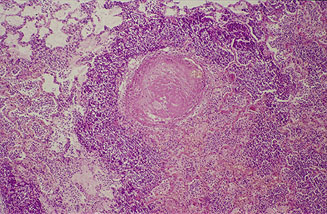

En las áreas pulmonares afectadas de la forma

aguda, se observa una intensa congestión, hemorragia

y edema alveolar. En estos territorios los septos

interlobulillares aparecen engrosados a causa del edema

intersticial, con los vasos linfáticos dilatados,

y presencia de células inflamatorias y eritrocitos

entre las redes de fibrina (Fig.

5).

Los alvéolos contienen células inflamatorias,

células descamadas y fibrina. Las

lesiones características consisten en áreas

de necrosis por coagulación asociadas con vasculitis

y trombosis. Alrededor de los focos de necrosis

destaca una franja celular basófila formada por

acúmulos de leucocitos degenerados de aspecto fusiforme,

identificados como macrófagos y neutrófilos,

que llenan las luces alveolares (Fig.

6).

Las lesiones en vías aéreas de conducción

se manifiestan en forma de exudados bronquiolares compuestos

por células epiteliales, células inflamatorias

degeneradas y fibrina. La pleuritis en el periodo agudo

es serofibrinosa con linfangiectasias en el parénquima

subyacente.

Fig. 5

Fig. 6